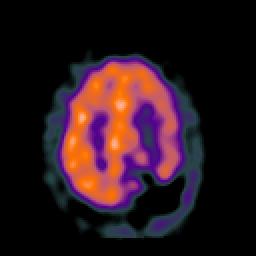

SPECT TC Study #2 -- Slice #39

[Home][Help][Clinical][Tour 1][Tour 2][Tour 3] Slice 39